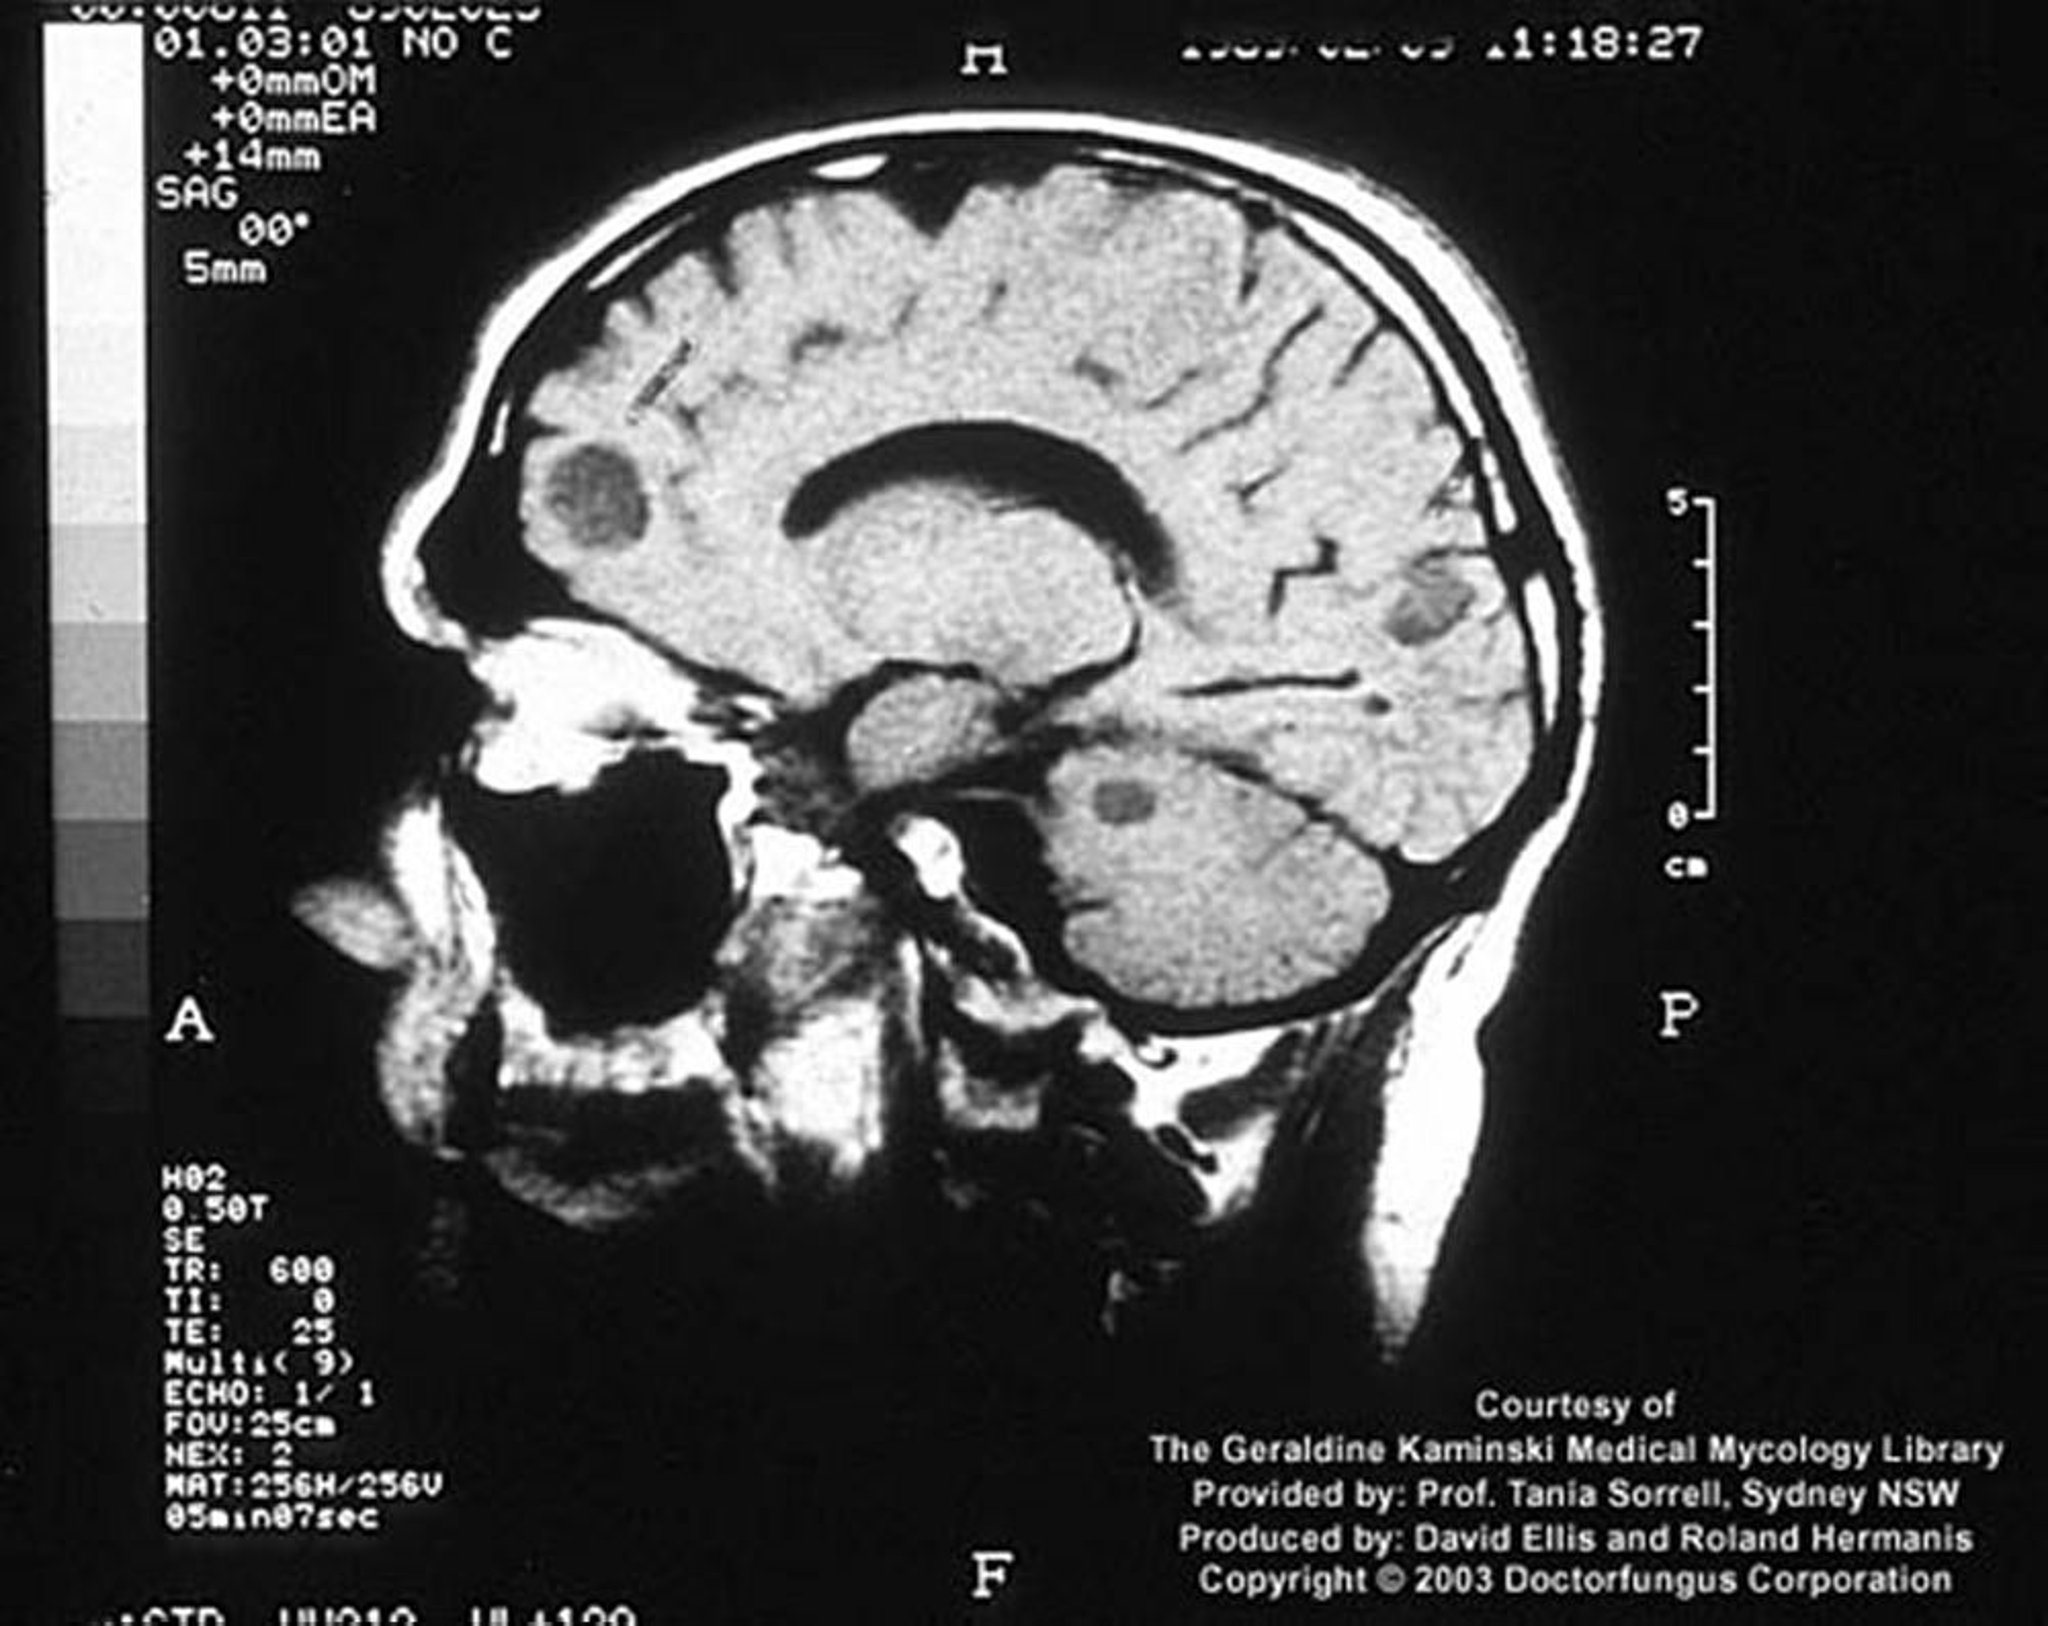

Cryptococcosis (Central Nervous System)

In an immunosuppressed host, cryptococcal infection may manifest as focal brain lesions called cryptococcomas.

Image courtesy of www.doctorfungus.org © 2005.